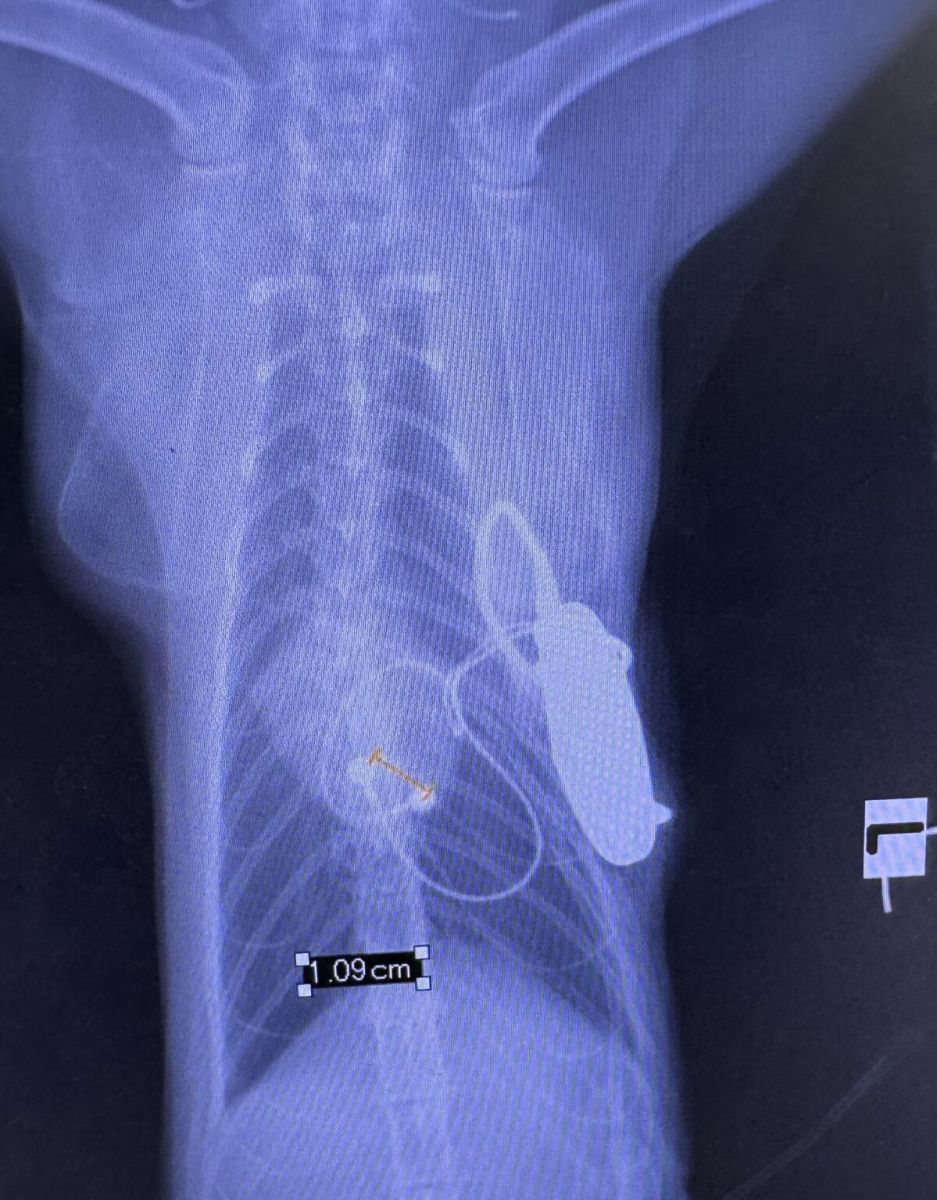

รศ.น.สพ.ดร.อนุศักดิ์ อธิบายถึงการผ่าตัดฝังเครื่องกระตุ้นหัวใจในแมวว่ามีความท้าทายมากกว่าในสุนัข เนื่องจากในสุนัขสามารถสอดสาย Pacemaker เข้าไปทางหลอดเลือดดำที่คอได้ แต่ในแมวนั้น กล้ามเนื้อหัวใจมีความหนาเพียงประมาณ 2 มิลลิเมตร ในขณะที่ความยาวของหมุดที่ใช้จิ้มเข้าไปในกล้ามเนื้อหัวใจมีความยาว 1.8 มิลลิเมตร ทำให้มีความเสี่ยงที่หมุดจะทะลุผ่านกล้ามเนื้อหัวใจได้ นอกจากนี้ขนาดของหลอดเลือดดำในแมวยังเล็กเกินไปสำหรับการสอดสายเข้าไป

“ทีมสัตวแพทย์ต้องใช้วิธีการเปิดช่องอกระหว่างกระดูกซี่โครงเพื่อเข้าถึงหัวใจโดยตรง จากนั้นจึงนำสายที่ใช้กระตุ้นหัวใจไปแปะไว้บนผิวของหัวใจ และเชื่อมต่อกับตัวเครื่องปล่อยกระแสไฟฟ้าที่ฝังไว้ใต้กล้ามเนื้อบริเวณช่องท้อง วิธีการนี้แม้จะซับซ้อนกว่าแต่ก็ปลอดภัยกว่าสำหรับแมวและสุนัขขนาดเล็ก การผ่าตัดครั้งนี้เป็นการปรับปรุงเทคนิคการฝังเครื่องกระตุ้นหัวใจจากเคสแรกที่ทำสำเร็จในน้องแมวไปเมื่อสองสัปดาห์ก่อนหน้า โดยเปลี่ยนจากการผ่าตัดทางกระบังลมมาเป็นการเปิดช่องอกระหว่างซี่โครง ทำให้การฝังเครื่องกระตุ้นหัวใจทำได้ง่ายและแม่นยำกว่า การผ่าตัดดำเนินไปด้วยดีโดยใช้เวลาประมาณหนึ่งชั่วโมง ความสำเร็จนี้เป็นผลมาจากการทำงานร่วมกันของทีมสหสาขาวิชาชีพ ประกอบด้วยทีมโรคหัวใจที่ทำการวินิจฉัย ทีมศัลยแพทย์ ทีมวิสัญญี และทีม Intervention ที่มีความเชี่ยวชาญเฉพาะทางด้านโรคหัวใจและหลอดเลือด รวมทั้งสิ้นประมาณ 4 ทีมที่ประสานงานกันอย่างใกล้ชิด” รศ.น.สพ.ดร.อนุศักดิ์กล่าว

รศ.น.สพ.ดร.อนุศักดิ์ กล่าวต่อไปว่า อุปกรณ์ที่ใช้ในการผ่าตัดเป็นอุปกรณ์เดียวกับที่ใช้ในคน เพียงแต่ต้องเลือกขนาดและความยาวของสายให้เหมาะสมกับขนาดของสัตว์ ตัวเครื่องปล่อยกระแสไฟฟ้ามีราคาประมาณ 45,000 บาท ส่วนสายมีราคากว่า 10,000 บาท ในเคสของน้องเป๊ปซี่โชคดีที่มีผู้บริจาคเครื่องปล่อยกระแสไฟฟ้า ซึ่งสามารถนำมาฆ่าเชื้อและใช้ซ้ำได้ ทำให้ช่วยลดค่าใช้จ่ายให้กับเจ้าของได้อย่างมาก ซึ่งผลการผ่าตัดเป็นที่น่าพอใจอย่างยิ่ง น้องเป๊ปซี่ไม่มีอาการเป็นลมอีกเลยหลังจากได้รับการผ่าตัด และสามารถกลับมาใช้ชีวิตได้ตามปกติ ไม่มีอาการอ่อนแรงอีกต่อไป สามารถเล่นกับเจ้าของและแมวตัวอื่นในบ้านได้ ไม่ซึม กินอาหารได้ปกติ และมีคุณภาพชีวิตที่ดีขึ้นอย่างเห็นได้ชัด อย่างไรก็ตาม เนื่องจากเครื่องกระตุ้นหัวใจเป็นอุปกรณ์ทางไฟฟ้าจึงมีความจำเป็นต้องนำน้องเป๊ปซี่เข้ามาตรวจสุขภาพและปรับแต่งเครื่องทุก 3 เดือน เพื่อให้แน่ใจว่าเครื่องยังทำงานได้ปกติ